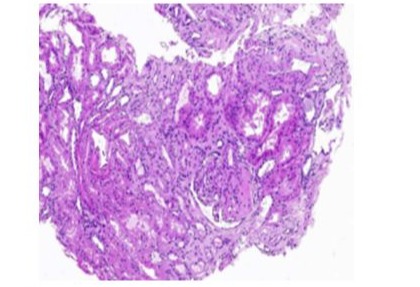

-A right renal biopsy was performed, yielding 10 glomeruli, a light microscopy revealed a segmental and focal glomerulosclerosis (FSGS) with no chronic lesions and no evidence of immune-mediated glomerulonephritis, morphological classification of FSGS (COLOMBIA): NOS (Figure 3).The electron microscopy showed podocyte foot process effacement typical lesion found inFSGS (Figure 4) and the immunofluorescence: IgA, IgG, IgM, C3, C1q was negative .

Figure 3: light microscopic study of kidney biopsy showing FSGS.

Recent discoveries have found that the PAX2 gene is re-expressed in nephropathy and acts as a suppressor of WT1, an important transcription factor of podocytes. Its mutation causes congenital nephrotic syndrome and FSGS [19]. In immune kidney diseases, Letavernier et al observed changes in podocyte phenotypes in focal segmental glomerulosclerosis (FSGS) and found that PAX2 is implicated in the pathogenesis of renal interstitial fibrosis and glomerulosclerosis [20]. Zhang et al found that in primary nephrotic syndrome, PAX2 expression in renal tubules in steroid-resistant children was significantly increased compared to steroid-sensitive children [21]. In 2014, PAX2 was found to be associated with adult-onset focal segmental glomerulosclerosis (FSGS) and was listed as a causative mutation of FSGS [22; 23]. In our case, the patient has proteinuria and FSGS in the kidney biopsy as shown in pictures 2-3. According to a recent Korean study, including 27 patients with PAX2 mutations detected from 2004–2022, 4 of them had FSGS [24].